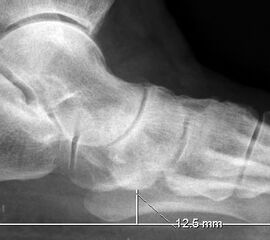

Auf der seitlichen, stehenden Aufnahme des Fußes wird ebenfalls der laterale Talo-Metatarsale I Winkel (Abb. 6 d) gemessen und so das kollabierte mediale Längsgewölbe dokumentiert. Auch hier gilt ein Talo-Metatarsale I Winkel von > 5° (nach plantar konvex) als pathologisch 21. Der Kollaps findet dabei meist im Talonaviculargelenk, seltener in der Naviculocuneiform-Gelenkreihe statt. Instabilität und Arthrose im 1. TMT sollten ausgeschlossen oder bei der Operationsplanung mit einbezogen werden. Weitere wichtige radiologische Messungen zur Beurteilung der Planovalgus-Statik und Progression der Deformität sind der laterale talo-calcaneare Winkel (Abb. 6 e) und der Abstand des Os cuneiforme-Unterrandes zum Untergrund (Abb. 6 f, Cuneiform height, 22. Eine anteriore Translation des Talus auf dem Kalkaneus findet man sowohl auf der ap, als auch auf der seitlichen Aufnahme des Fuβes mit Aufhebung der Cima-Linie.

„Cuneiforme height“ (Abb. 6f)